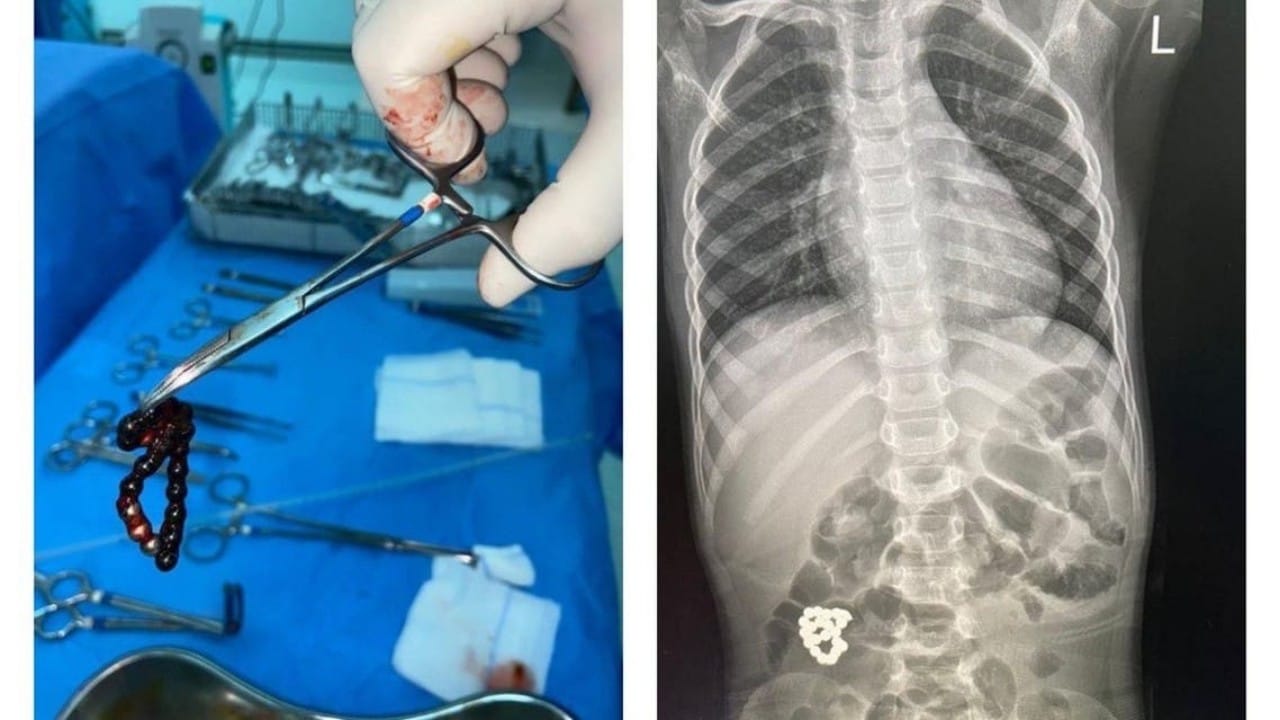

استخراج جسم غريب من أمعاء طفل في جدة